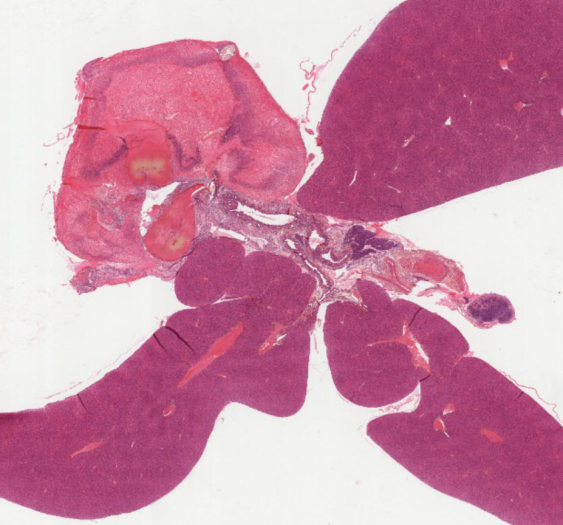

呼吸系统